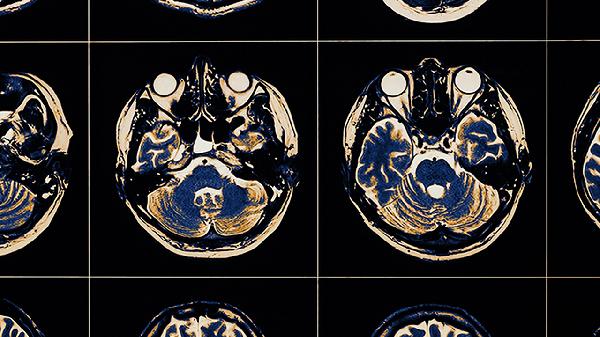

5、血管性痴呆

对多发性脑梗死导致的认知功能下降可能有一定改善作用。临床表现为记忆力减退、计算力下降等,需与阿尔茨海默病鉴别。通常与奥拉西坦胶囊、尼麦角林片等改善脑代谢药物联用。